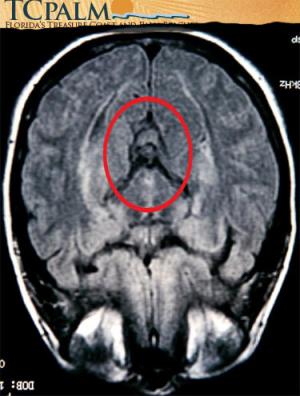

Exame feito em 2002 reproduziria ícone do catolicismo.

Imagem religiosa em exame pode render dinheiro a americana. (Foto: Reprodução/TCPalm)

Foi a irmã de Pamela quem primeiro notou a semelhança da área do cérebro reproduzida na tomografia, realizada em 2002, com a imagem da santa.